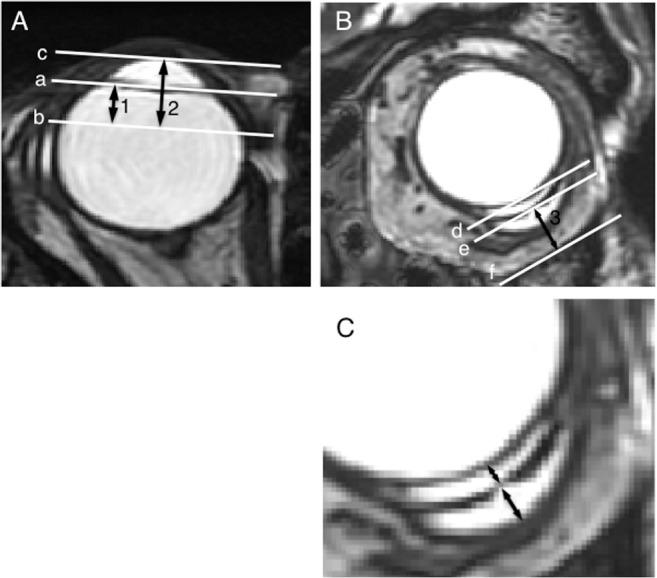

This observational case series included 27 consecutive glaucomatous eyes (18 men, 7 women; mean age ± standard error, 63.0±2.0 years) who underwent GDD implantation (n = 8 Ahmed Glaucoma Valves [AGV] and n = 19 Baerveldt Glaucoma Implants [BGI]). Tubes were inserted into the pars plana in 23 eyes and anterior chamber in 4 eyes. Six months postoperatively, high-resolution orbital images were obtained using 3-Tesla MRI with head-array coils, and the filtering bleb volume, bleb height, and distances between the anterior endplate edge and corneal center or limbus or between the endplate and orbital wall were measured.

In MR images obtained by three-dimensional fast imaging employing steady-state acquisition (3D-FIESTA) sequences, the shunt endplate was identified as low-intensity signal, and the filtering bleb was identified as high-intensity signals above and below the endplate in all eyes. The 6-month-postoperative IOP level was correlated negatively with bleb volume (r = -0.4510, P = 0.0182) and bleb height (r = -0.3954, P = 0.0412). The postoperative IOP was significantly (P = 0.0026) lower in BGI-implanted eyes (12.2±0.7 mmHg) than AGV-implanted eyes (16.7±1.2 mmHg); bleb volume was significantly (P = 0.0093) larger in BGI-implanted eyes (478.8±84.2 mm3) than AGV-implanted eyes (161.1±52.3 mm3). Other parameters did not differ.